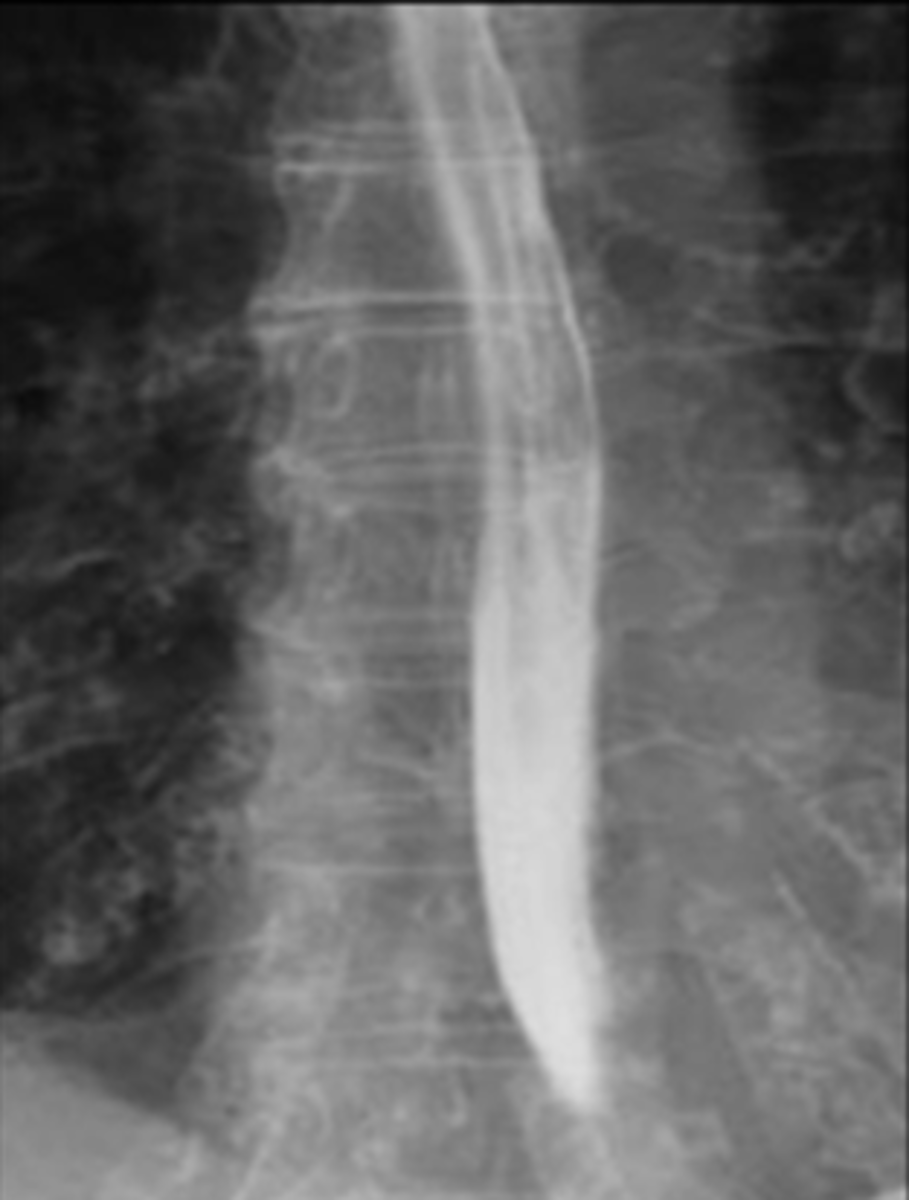

Achalasia - classic finding on barium studies is the bird's beak

Achalasia

Normal

Achalasia barium swallow